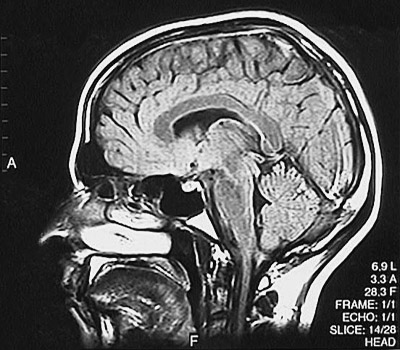

This is a normal sagittal FLAIR MRI scan demonstrating the view just left of midline with the frontal lobe and parietal lobe and occipital lobe and cerebellum and genu of corpus callosum and splenium of corpus callosum and thalmus and midbrain and pons and medulla and cervical spinal cord and tongue and nasal cavity.